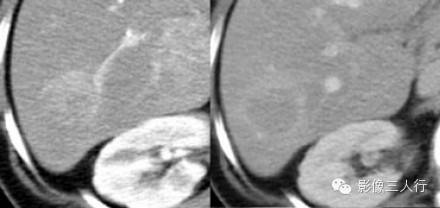

富血管病变在动脉期的表现非常类似(图)。鉴别需要与其他时相的强化表现以及病理和临床相结合。富血供转移瘤的患者需要结合原发肿瘤。肝癌好发于肝硬化患者,FNH多见于年轻妇女,肝腺瘤病人有口服避孕药、合成代谢类固醇或有糖原贮积症的病史。

下图:增强动脉期四种不同的肿瘤。从左到右:肝硬化肝癌;年轻女性的FNH(中央疤痕);腺瘤(年轻女性口服避孕药)和血管瘤的典型增强(其它期未显示)